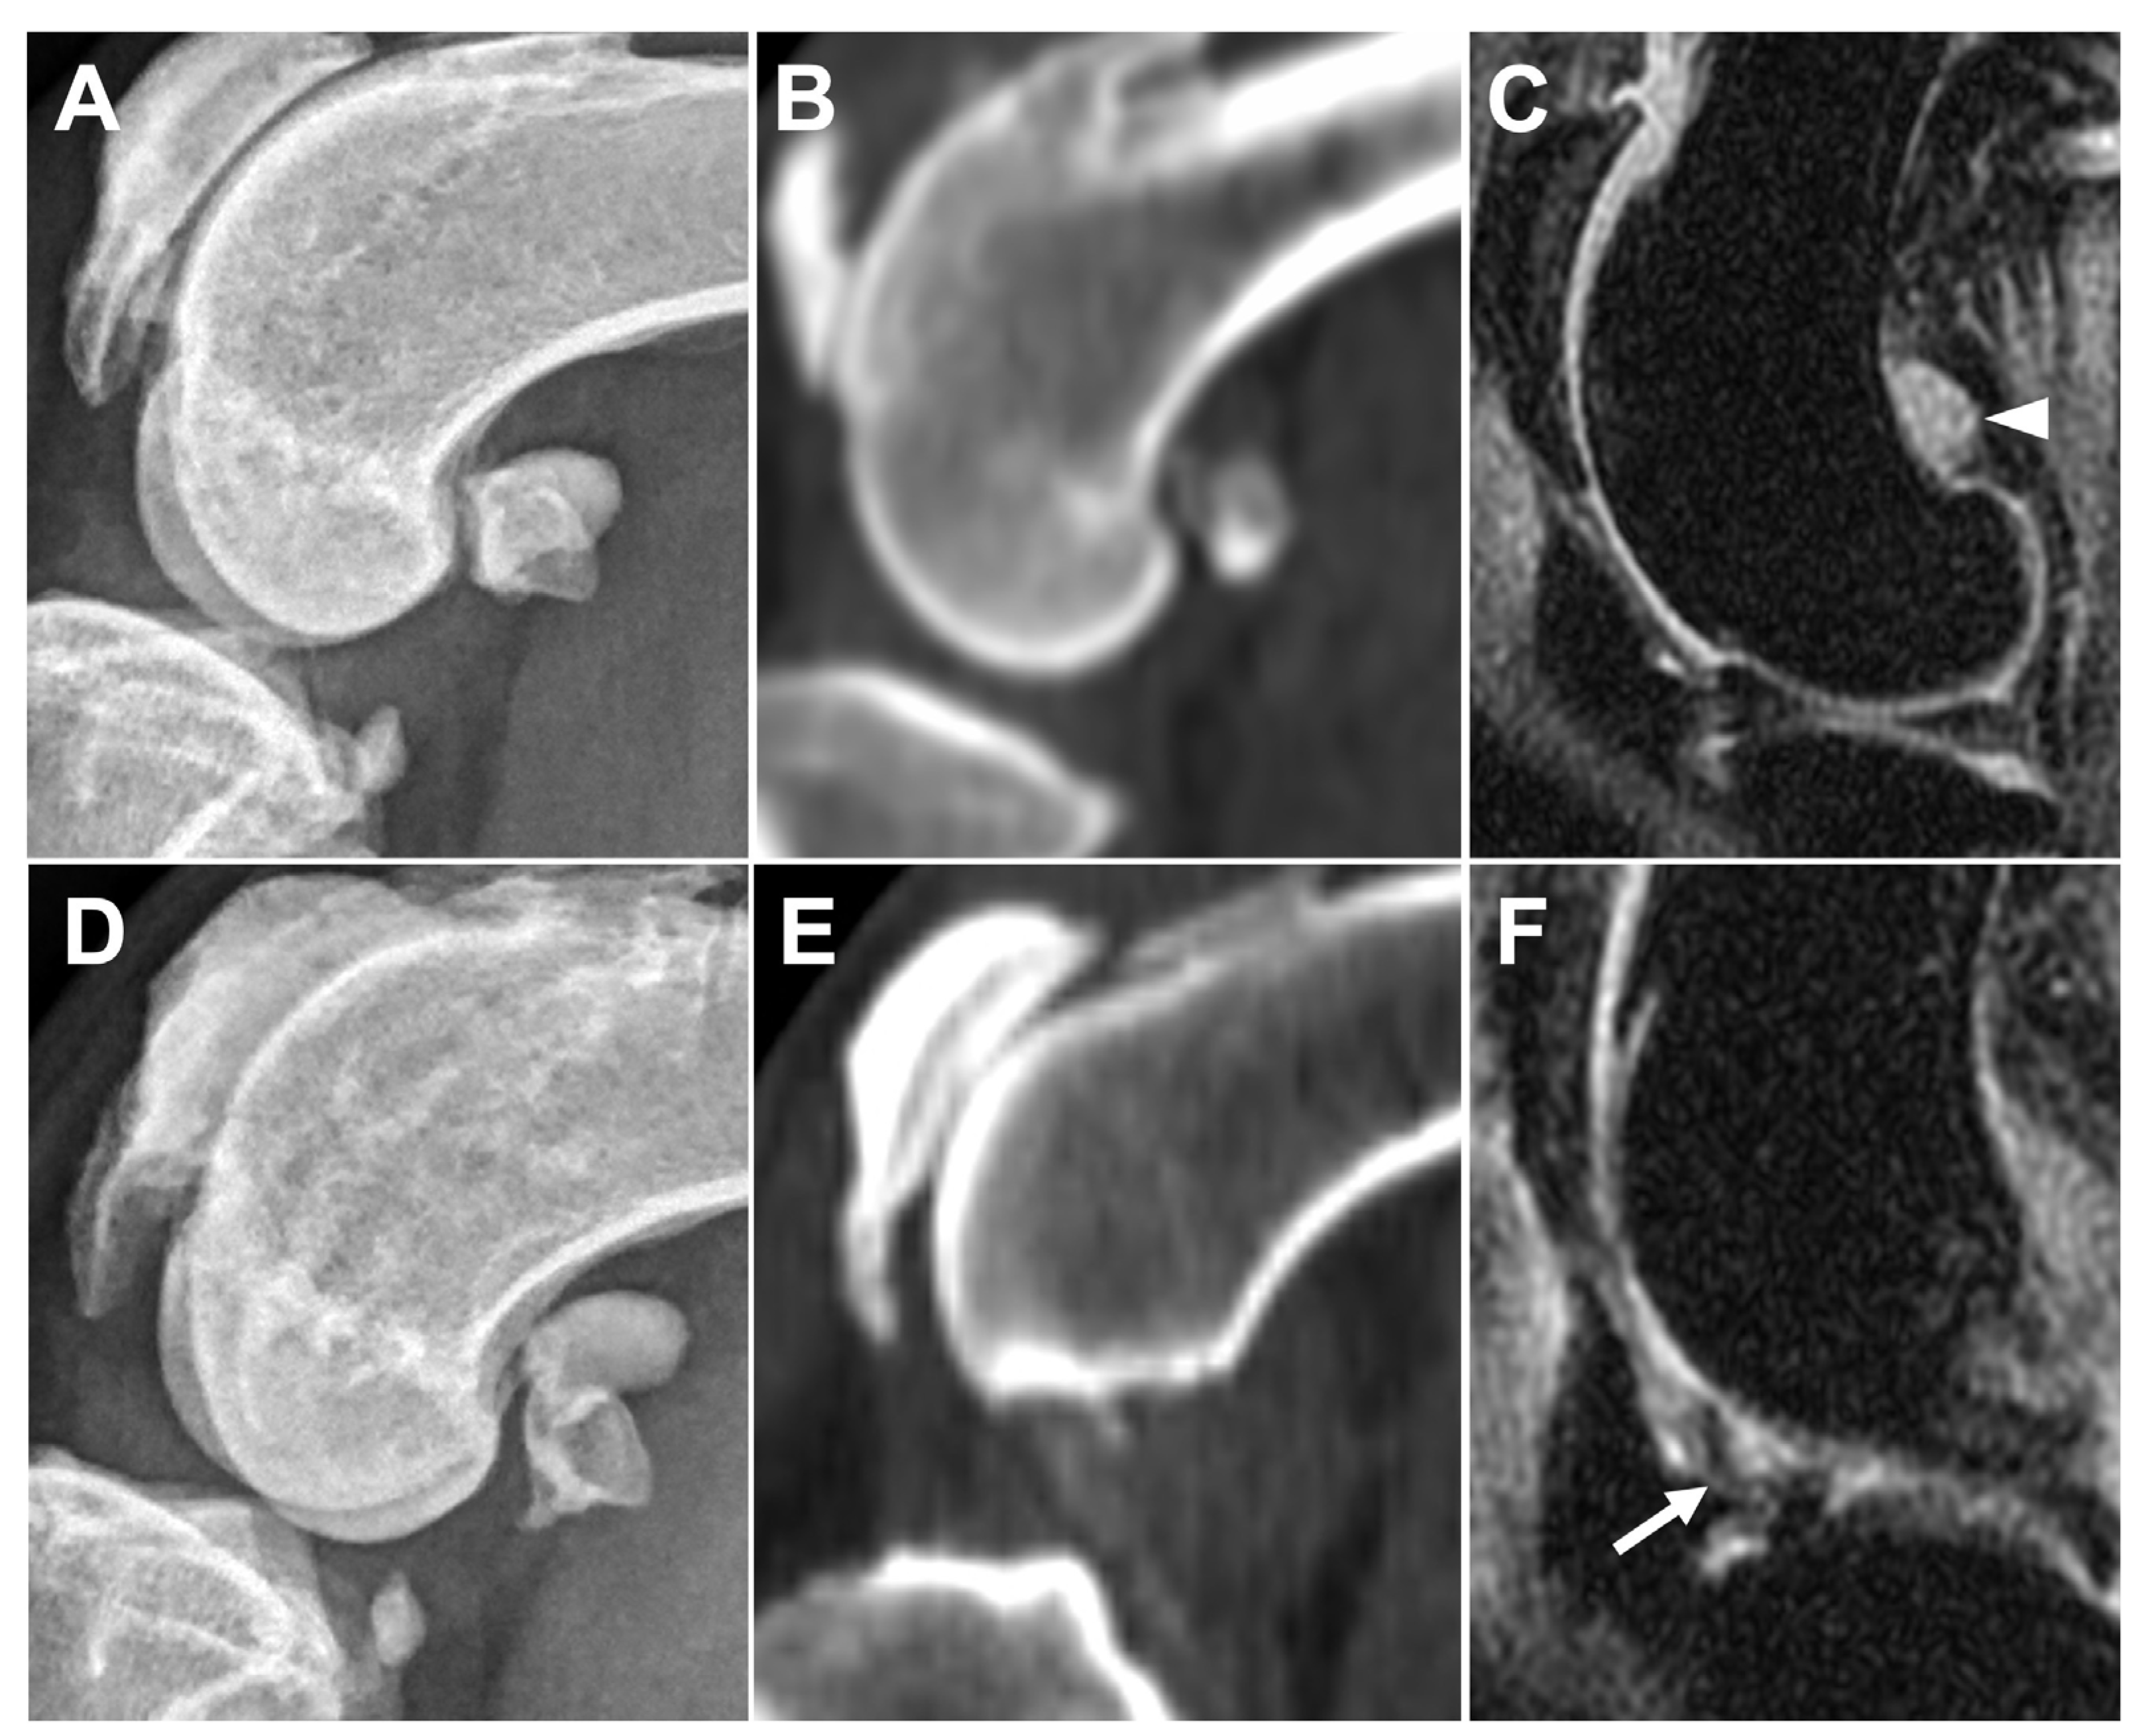

3.2.2. Ligament/Tendon Lesions

3.2.3. Synovial Effusion and Membrane Thickening

3.2.4. Subchondral Bone Lesions

3.2.5. Meniscal and Cartilage Lesions